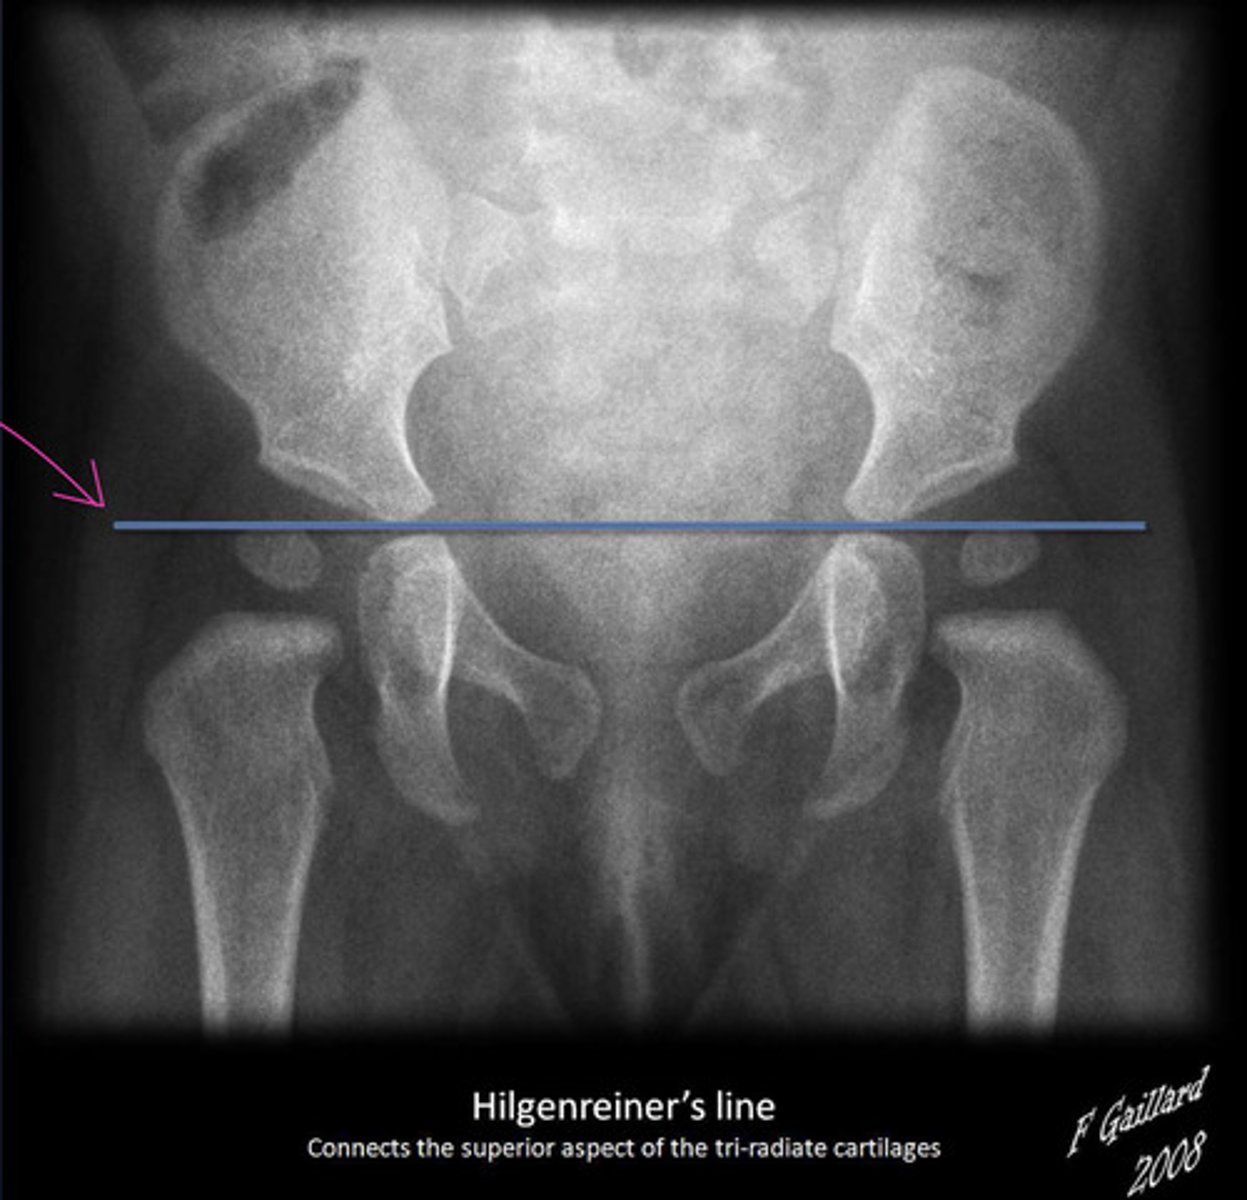

Hilgenreiner's Line

Used for assessment of DDH

Line drawn horizontally, connecting the inferior aspect of the tri-radiate cartilages bilaterally >> femoral head should be below this line

Perkin's Line

Line drawn vertically through the lateral most aspect of the acetabular roof perpendicular to Hilgenreiner's line

The ossified femoral head should be located in the inferomedial quadrant created